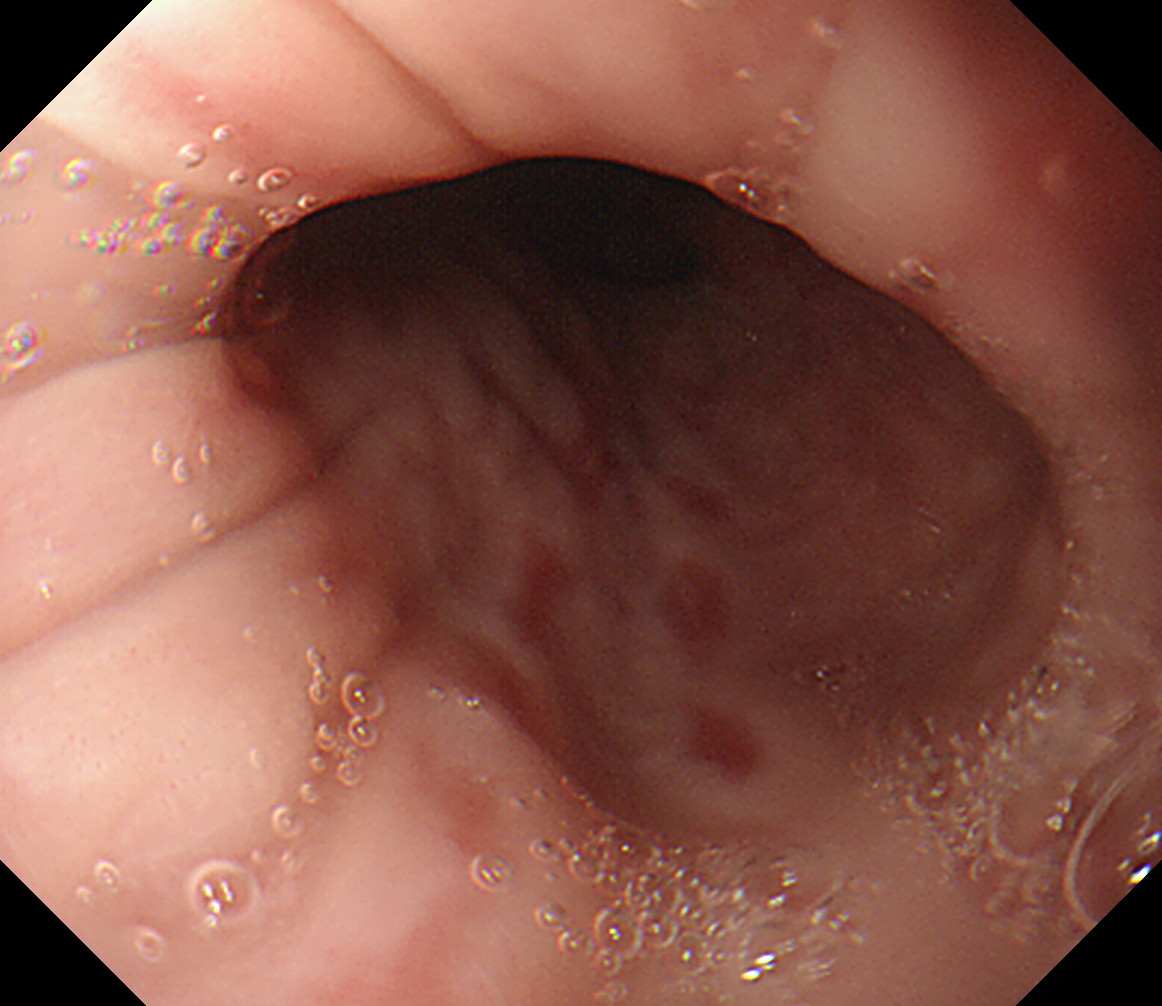

8 幽門輪 いわゆる「PーRing」 幽門輪

9 十二指腸球部前壁 十二指腸球部前壁

10 十二指腸球部後壁 この後十二指腸下降脚とVater乳頭を観察します 中部食道